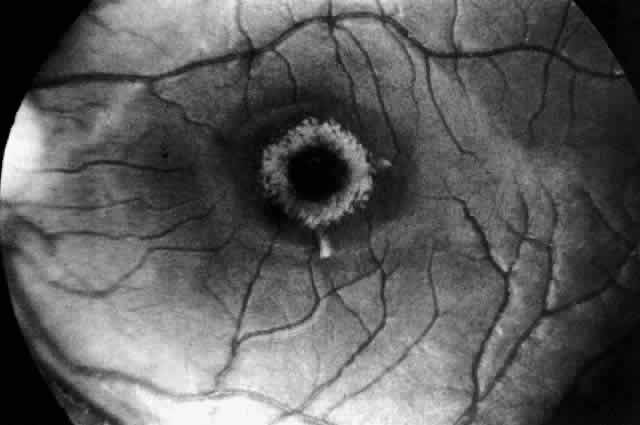

A more widespread opacification of the retina can occur due to involvement of the ganglion cells in the posterior pole. This was observed by Wray4 in a 3½-year-old child with Tay-Sachs disease. The child had black hair and brown eyes, and the cherry-red spot at the macula was brown. The patient was blind, with marked optic atrophy (Fig. 4).

Fig. 4. Fundus of 3 1/2-year-old girl with Tay-Sachs disease. Note cherry-red spot, an extensive white parafoveal halo, and optic atrophy.